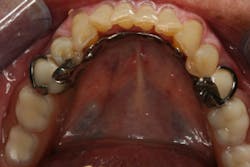

In this case, the diagnostic wax-up of the mounted models gave the technician the new position of the upper incisal edge. The technician then set the maxillary teeth appropriately using models and additional photographs. At the same time, tooth No. 20 was restored, but the lab technician kept the crown and lower partial to predictably create the lower occlusal plane and easily articulate this with the upper immediate denture (figure 18). Note the improved curve of Spee in Figures 19 and 20. Upon completion of the prosthesis, treatment was completed as outlined and the results made the patient feel very comfortable functionally, esthetically, and phonetically.

There was some fine-tuning to the patient's occlusion during the healing period. Nevertheless, the goals of treatment were accomplished very predictably. Figures 21 (horizontal position) and 22 (vertical position) verify both the new vertical and horizontal positions of the upper incisal edge.